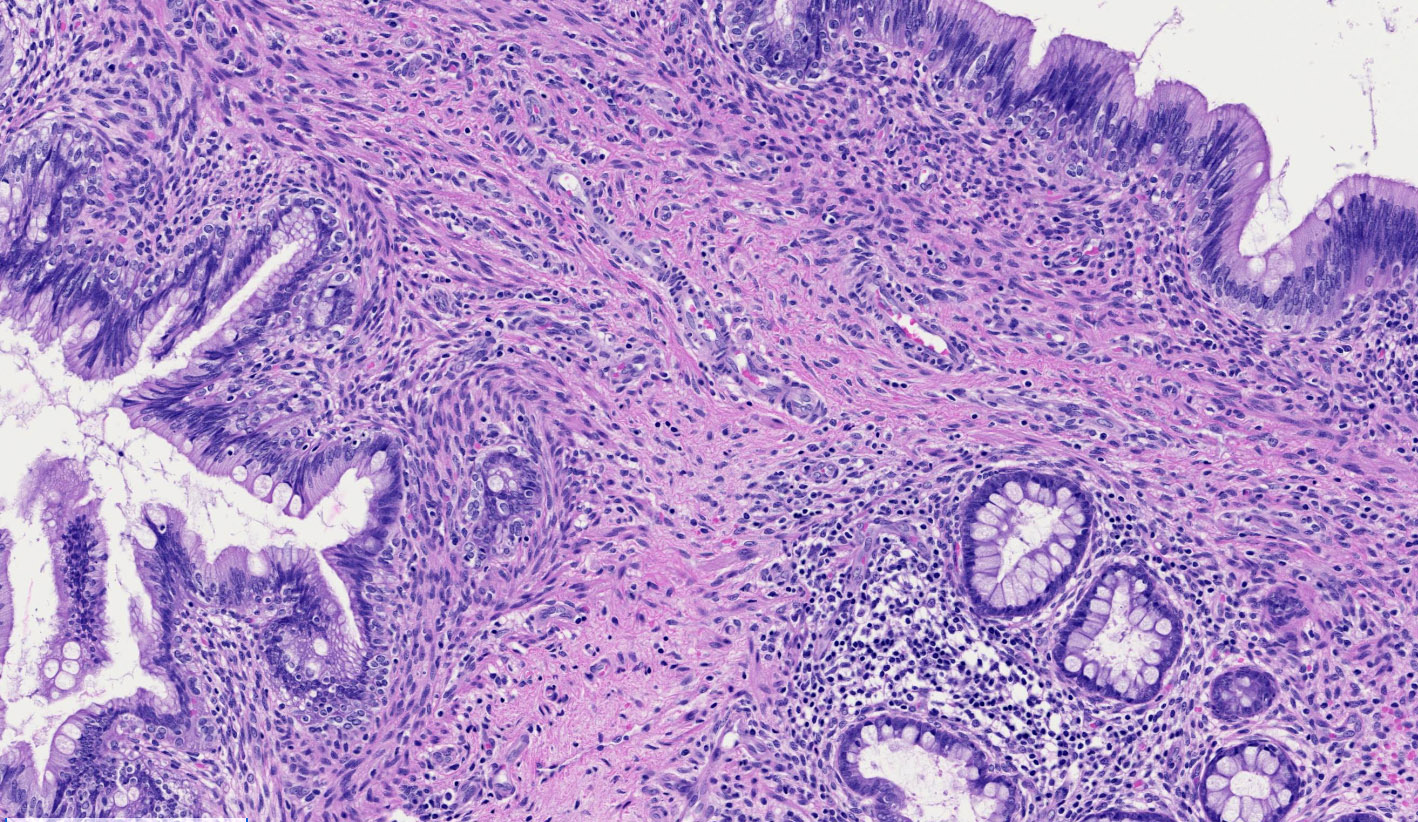

- Mixture of mature, benign tissues

- Ectodermal (most common): squamous epithelium, sebaceous glands, hair follicles, brain tissue

- Endodermal: intestinal or respiratory epithelium, thyroid, salivary gland

- Fat necrosis and foreign body reaction may be seen

- Cases associated with NMDAR encephalitis usually show neuroglial tissue associated with lymphoid aggregates with germinal centers, low number of mature neurons and a hypercellular astrocyte population (Am J Surg Pathol 2019;43:949)

Microscopic (histologic) images